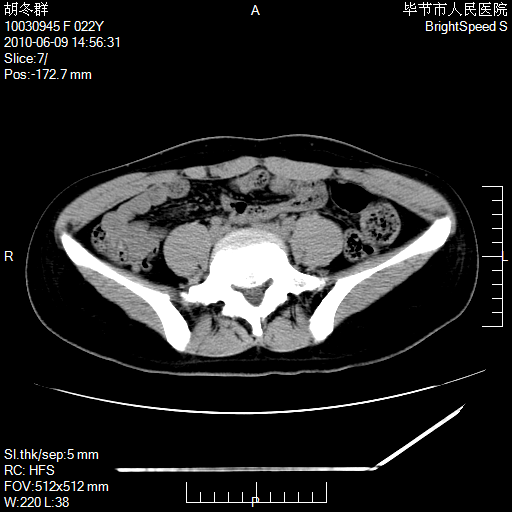

患者23岁,发现腹部包块3月。

盆腔内囊性占位;穿刺或者直接手术拿掉即可,不必紧张。

左侧卵巢囊腺瘤或囊腺癌

盆腔内囊性占位性病变;考虑左侧卵巢囊腺瘤。

有分隔、壁薄,支持考虑左侧卵巢囊腺瘤。

左侧卵巢浆液性囊腺瘤。

支持考虑左侧卵巢囊腺瘤;宫腔积液。

有分隔、壁薄,支持考虑左侧卵巢囊腺瘤。排尿后,膀胱缩小,由于重力作用,肿块下移就到了膀胱位置,很好理解。